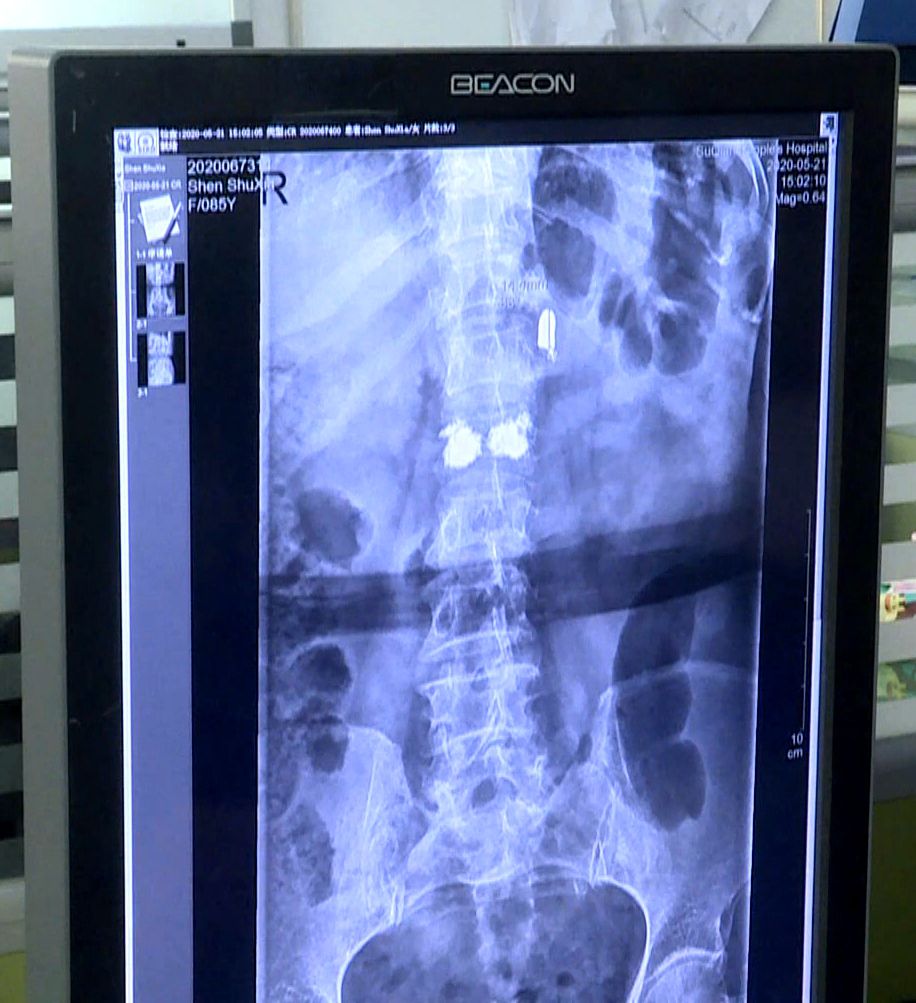

江苏省宿迁市的85岁老人沈书侠近日遭遇车祸 , 腰椎骨折 。 医生手术透视过程中 , 在老人背部发现了一枚子弹 , 直径8毫米左右 , 长度15毫米左右 , 像是手枪的子弹 。 老人这才回想起日本侵略者进村扫荡时 , 自己后背受伤侥幸存活 , 没想到子弹在体内留存了80年 。

【社会万象85岁老人体内发现80年前日军子弹 见证当年血泪史】沈书侠老人回忆 , 自己小时候生活的“陈庄”就是现在的宿迁市宿城区双庄街道附近 , 日军前来扫荡 , 在她家里纵火 , 并残忍杀害了她的母亲 , 哥哥慌乱中抱着5岁的自己准备跳墙逃跑 , 在墙头上被日军一枪给打下来了 , 哥哥中枪后当场死亡 , 沈书侠后背也受伤流血 , 估计子弹在当时已经射进了沈书侠的体内 。

沈书侠昏迷中侥幸存活 , 事后被亲戚收养 , 抚育成人 。 八十年来 , 失去家人的伤痛和童年的阴影一直伴随着沈书侠老人 , 但她从没想到自己体内还有一颗子弹 。 尽管偶尔会感觉到腰部隐隐作痛 , 但总认为是自己腰不好 。 由于子弹头潜藏较深 , 距离老人的腰椎和其他器官较近 , 加上老人年事已高 , 手术具有一定风险性 , 医生不建议将子弹头取出 。